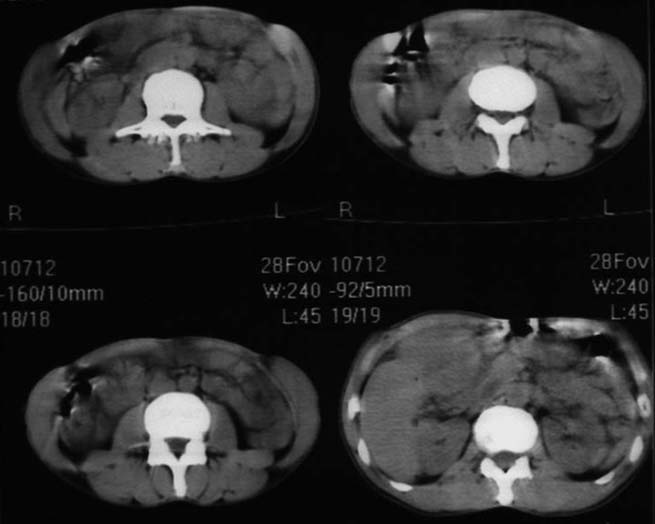

男,50y,右上腹包块痛10天,查:右上腹饱满,右肋下触及6*6cm大小包块,质硬,压痛。患者诉:10天前感冒胸闷,痛,后痛及右上腹部,既往有肝炎病史。

没有增强!只能考虑左叶内侧段巨块型肝癌(外生型)可能性大;胆囊呢?不除外胆囊癌累及肝脏。

我倒是先考虑胆囊癌(肿块型)肝脏受侵可能性大,做个c+

病变位于胆囊窝内,其内密度不均,肝总管及胆总管扩张,胃里面没有清水充盈,不解为什么楼主不做好了准备再做呢,支持:“左叶内侧段巨块型肝癌(外生型)可能性大;不除外胆囊癌累及肝脏”建议增强吧。

考虑:肝左内叶巨块型癌,主动脉旁淋巴结转移.(有一层面似见胆囊受压.)